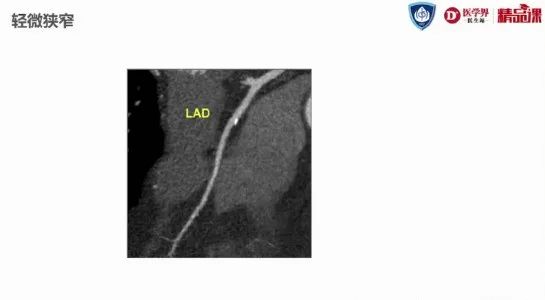

CCTA狭窄程度可分为正常、轻微、轻度、中度、重度和闭塞(图6)。其中有三个关键数字,分别是50%,70%和100%。狭窄50%以上为中度狭窄,70%以上为重度狭窄,100%为完全闭塞。

50%以上即可诊断冠心病,为诊断标准;70%以上即达到了经皮冠状动脉介入治疗(PCI)的标准;100%时PCI难度较大,在术前需要做好各种准备。

图6:轻微狭窄(<20%)示意图